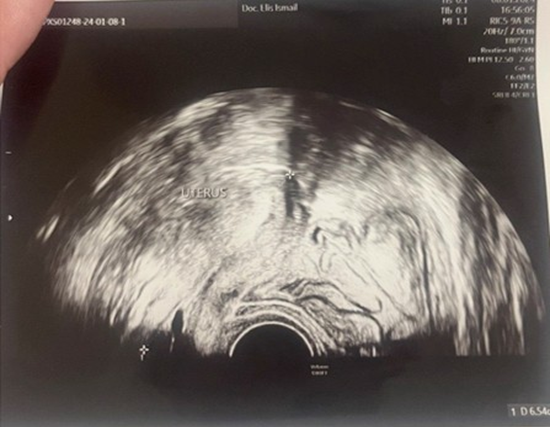

A 23-year-old asymptomatic female patient. During a routine gynecological examination, pelvic ultrasound identified a nonspecific tumor-like mass of solid consistency (Figures 1-3). The patient is sexually active and nulliparous. She has no history of abnormal menstrual bleeding or pelvic pain. Pelvic ultrasonography demonstrated a nonspecific tumor-like mass. The lesion was located in the vesicouterine space, anterior to the uterus (which was in anteversion and anteflexion with length 6.5 cm.) and posterior to the urinary bladder. The mass measured approximately 10 cm and had a predominantly solid component, with multilaminar hypoechoic bands within its capsule (Figures 1 and 4). Both ovaries were visualized and appeared normal on transvaginal ultrasonography (Figures 2 and 3). The pouch of Douglas is free of fluid.

Figure 1: Ultrasonographic image revealed a uterus of normal morphology, measuring 6.5 cm. in length.